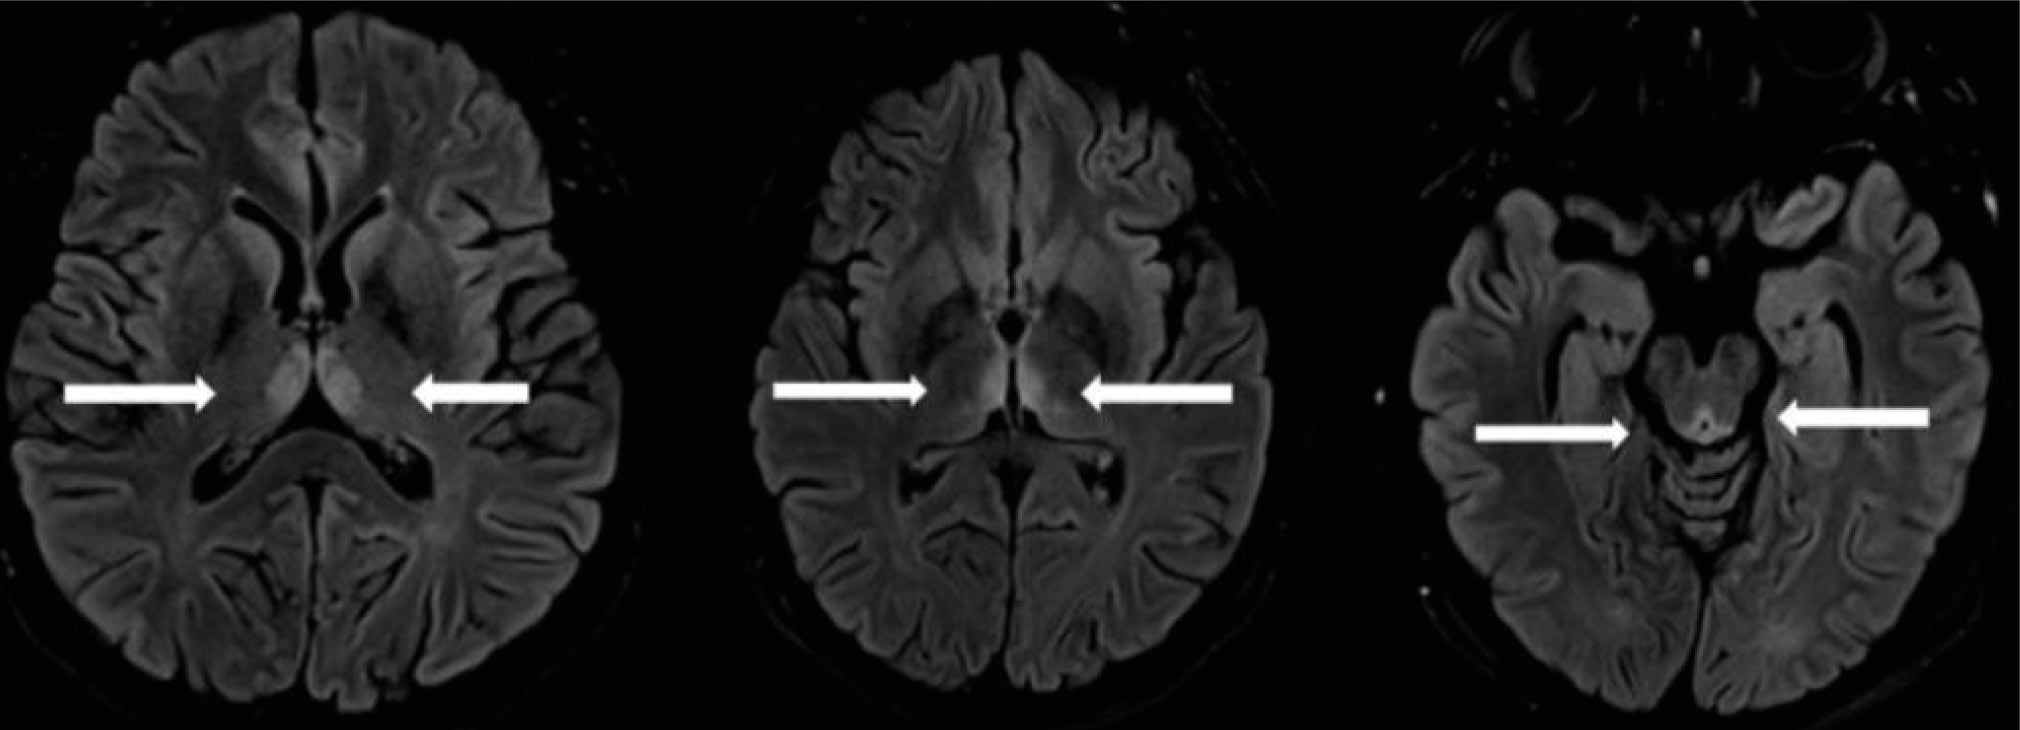

Brain magnetic resonance imaging (MRI) was performed on 14 June 2022 using T1- and T2-weighted FSE and SE protocols, FLAIR, DWI, SWI sequences. Midline structures were not shifted. Bilateral symmetrical areas of hyperintensity in T2 (SE and FLAIR) pulse sequences were observed in the dorsomedial thalamic nuclei and subependymal regions of the third ventricle and periaqueductal gray matter (Figure 1). The MRI findings could be considered in the context of Wernicke’s encephalopathy. No data suggestive of stroke were obtained.

Fig. 1. Magnetic resonance imaging of the brain (Patient K.) (cross-sectional image at the level of the III ventricle and mediodorsal nucleus of thalamus): the arrows indicate symmetrical MR signal enhancement.

The sensitivity of MRI in detecting Wernicke’s encephalopathy is 53%. However, the high specificity of 93% allows using MRI for the diagnosis of Wernicke encephalopathy. In Wernicke’s encephalopathy, brain MRI usually shows areas of bilateral symmetrical hyperintensity in T2 mode and decreased signal in T1 mode, as well as diffuse lesions around the aqueduct, third and fourth ventricles, midline of the cerebellum, and paraventricular regions of the thalamus, hypothalamus, and mammillary bodies [8].